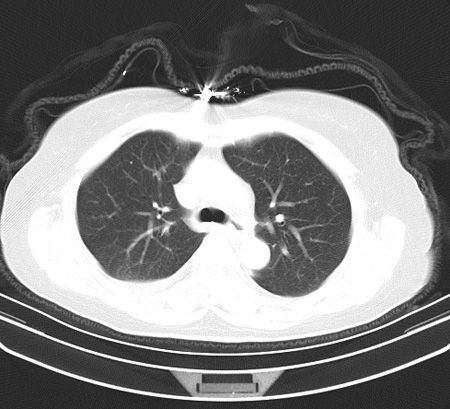

以下是引用余辉在2009-2-19 20:10:00的发言:[br]多考虑急性感染性病变,右中叶尚可见多枚小斑片状影,多为化脓性肺炎,双侧胸腔积液

以下是引用随光逐影在2009-2-19 20:33:00的发言:[br]1)考虑右肺炎症;建议抗炎治疗后复查。2)双侧胸腔积液(以右侧为甚)。

以下是引用花凤凰在2009-2-19 20:46:00的发言:[br]病人有发热,胸痛急性起病,主要病变位于右肺中叶外侧段,呈楔行改变,位于外带胸膜下,考虑为肺梗塞可能!!!!!!!!!!!!!!!!!!!!!!!!!!!!!!!!!!!